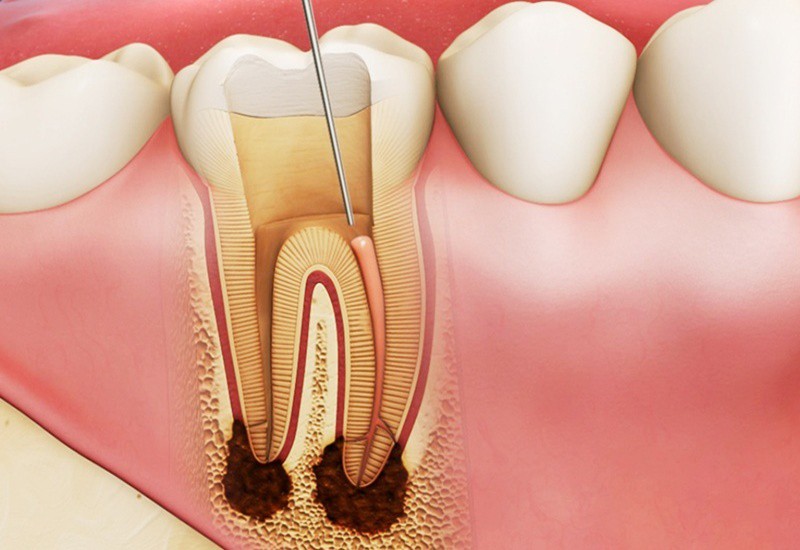

- Răng Bị Sâu

- Khi một chiếc răng bị sâu nghiêm trọng và hư tổn nặng nề, việc nhổ răng có thể là giải pháp cần thiết để ngăn ngừa sự lây lan của vi khuẩn và bảo vệ các răng khác.

- Răng Viêm Tủy

- Viêm tủy răng nếu không được điều trị kịp thời có thể dẫn đến viêm cuống răng, tổn thương chân răng và hoại tử tủy. Đôi khi, việc nhổ răng là cách duy nhất để giải quyết tình trạng này.